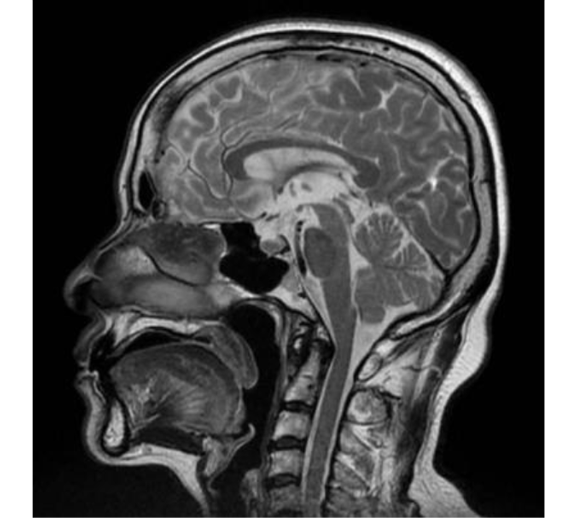

【脳ドック MR でわかる事】

脳腫瘍、脳梗塞、脳出血、脳動脈瘤(くも膜下出血の原因)、脳血管の閉塞や狭窄、 椎骨動脈解離、脳血管奇形、頸動脈狭窄など

脳動脈瘤(くも膜下出血の原因)

聴神経腫瘍